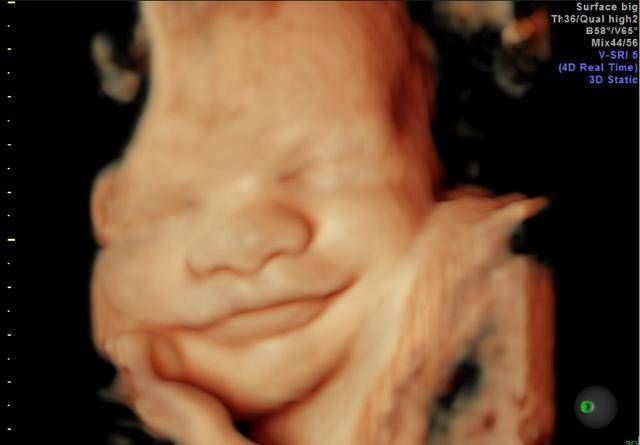

孕期产检,相信不少孕妈妈都很期待四维排畸这一项了,四维彩超排畸检查有不少准妈妈也想带着准爸爸进去,一同分享这其中的喜悦。

【为什么有些医院做四维彩超不让家属陪同这些原因,大家有权知道】小茹怀孕24周左右的时候,身边朋友提醒她这个时候需要做四维大排畸了,不仅能知道胎宝宝发育状况,还可以提前看到宝宝的长相。